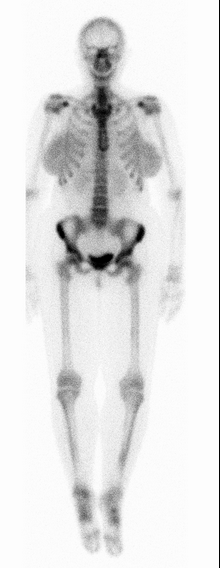

• Normal bone scan

• Increased uptake where there is trabecular (cortical) bone

• Spine for example

• Can faintly see kidneys

• Some uptake in bladder

• Mild symmetric uptake in breast

• Low level in soft tissues

• Epiphysis in kids

Superscan

• Diffuse uniform tracer uptake throughout the skeleton

• Will see concurrent decreased renal activity

• Most commonly due to prostate carcinoma

• Other things looking similar if no cancer —> hyperparathyroidism